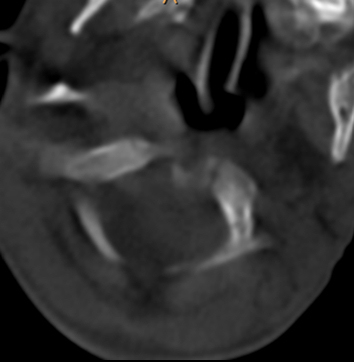

We referred to CT scanning to further localise the osseous malformation complex. Axial reformatted CT scan of C3 showed hypoplasia of the vertebral body associated with defective ossification of the pedicle, lamina and the spinous process respectively (Figure 2 [Fig. 2]). Sagittal reformatted CT scan showed occipitalisation of the anterior arch of the atlas, anterior and horizontal atlantoaxial dislocation associated hypoplasia of the vertebral bodies (Figure 3 [Fig. 3]). 3 D reconstructions CT scan showed significant disconnection of the posterior spine elements (arrow) related to underdeveloped pedicles and hypoplasia of the laminae along different cervical levels C2/4 and C6 associated with extensive malsegmentation (Figure 4 [Fig. 4]). Sagittal MRI showed the atrophic spinal cord at C7/T1 (in this patient there was a constellation of spinal osseous maldevelopment of the cervico-thoracic vertebrae with subsequent development of traumatic atrophy of the spinal cord) (Figure 5 [Fig. 5]).